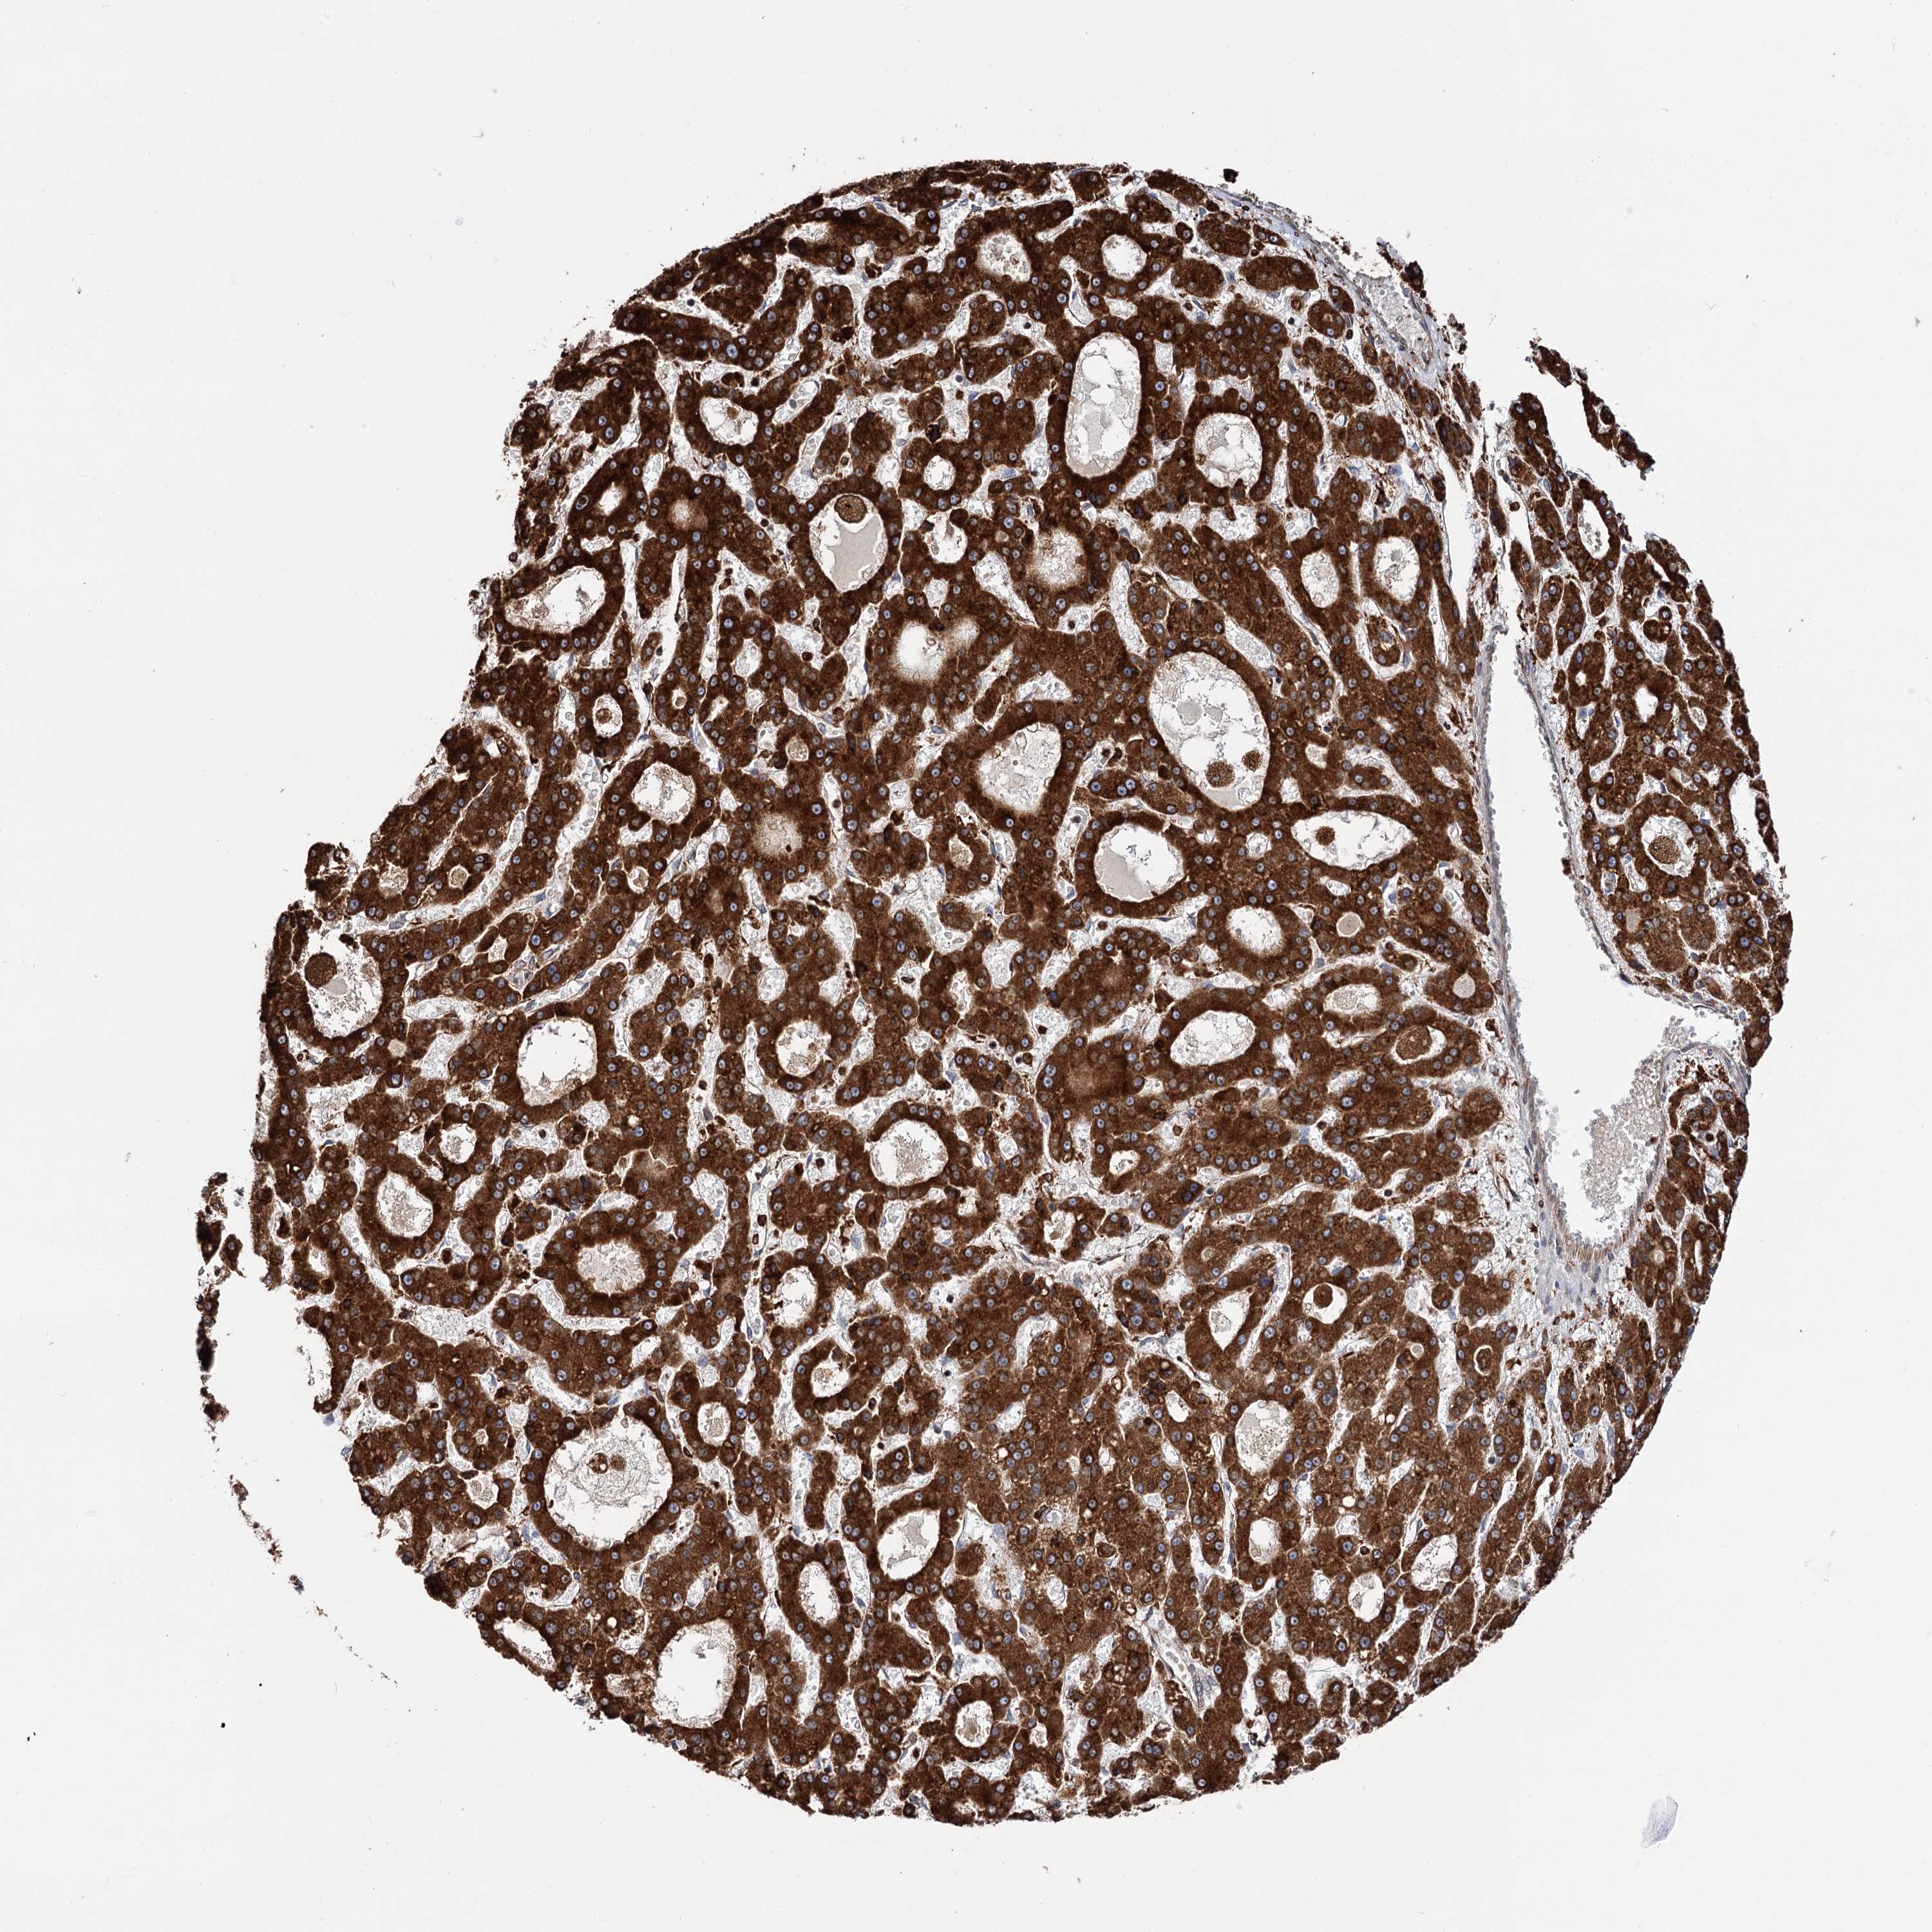

LIVER CANCER - Protein expressioni

A mouse-over function shows sample information and annotation data. Click on an image to view it in a full screen mode. Samples can be filtered based on level of antibody staining by selecting one or several of the following categories: high, medium, low and not detected. The assay and annotation is described here.

Note that samples used for immunohistochemistry by the Human Protein Atlas do not correspond to samples in the TCGA dataset.

Antibody stainingi

Antibody staining in the annotated cell types in the current human tissue is reported as not detected, low, medium, or high, based on conventional immunohistochemistry profiling in selected tissues. This score is based on the combination of the staining intensity and fraction of stained cells.

Each image is clickable and will lead to virtual microscopy that enables deeper exploration of all samples and also displays staining intensity scores, fraction scores and subcellular localization as well as patient and tissue information for each sample.

Antibody HPA039363

Antibody HPA039456

Staining

High

Medium

Low

Not detected

Intensity

Strong

Moderate

Weak

Negative

Quantity

>75%

75%-25%

<25%

None

Location

Nuclear

Cytoplasmic/membranous

Cytoplasmic/membranous,nuclear

Cholangiocarcinoma

Carcinoma, Hepatocellular, NOS